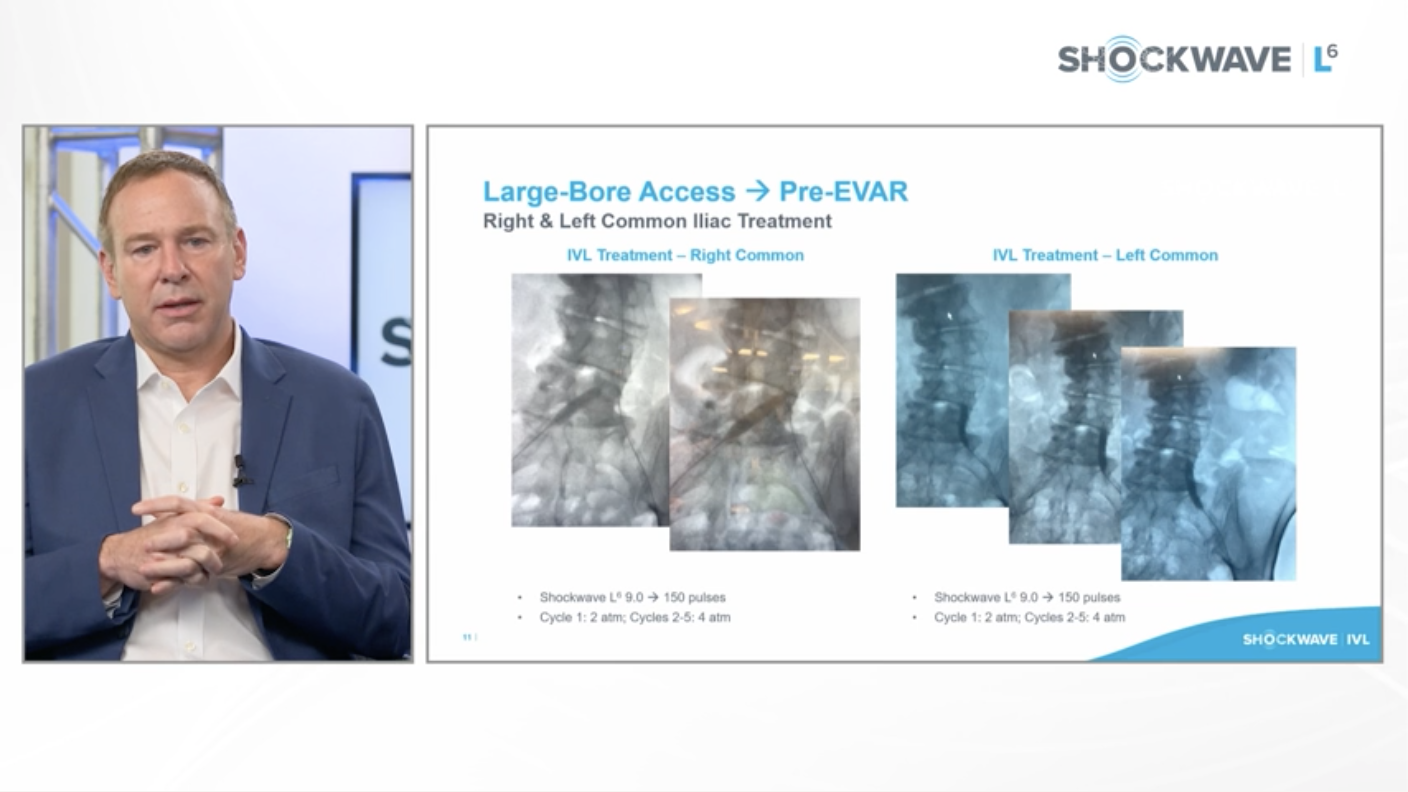

Introducing Shockwave L6 Peripheral IVL Catheter. Now Available in United States and Coming Soon to EU

Introducing Shockwave L6 Peripheral IVL Catheter. Now Available in United States

IVL to facilitate Transfemoral TAVI